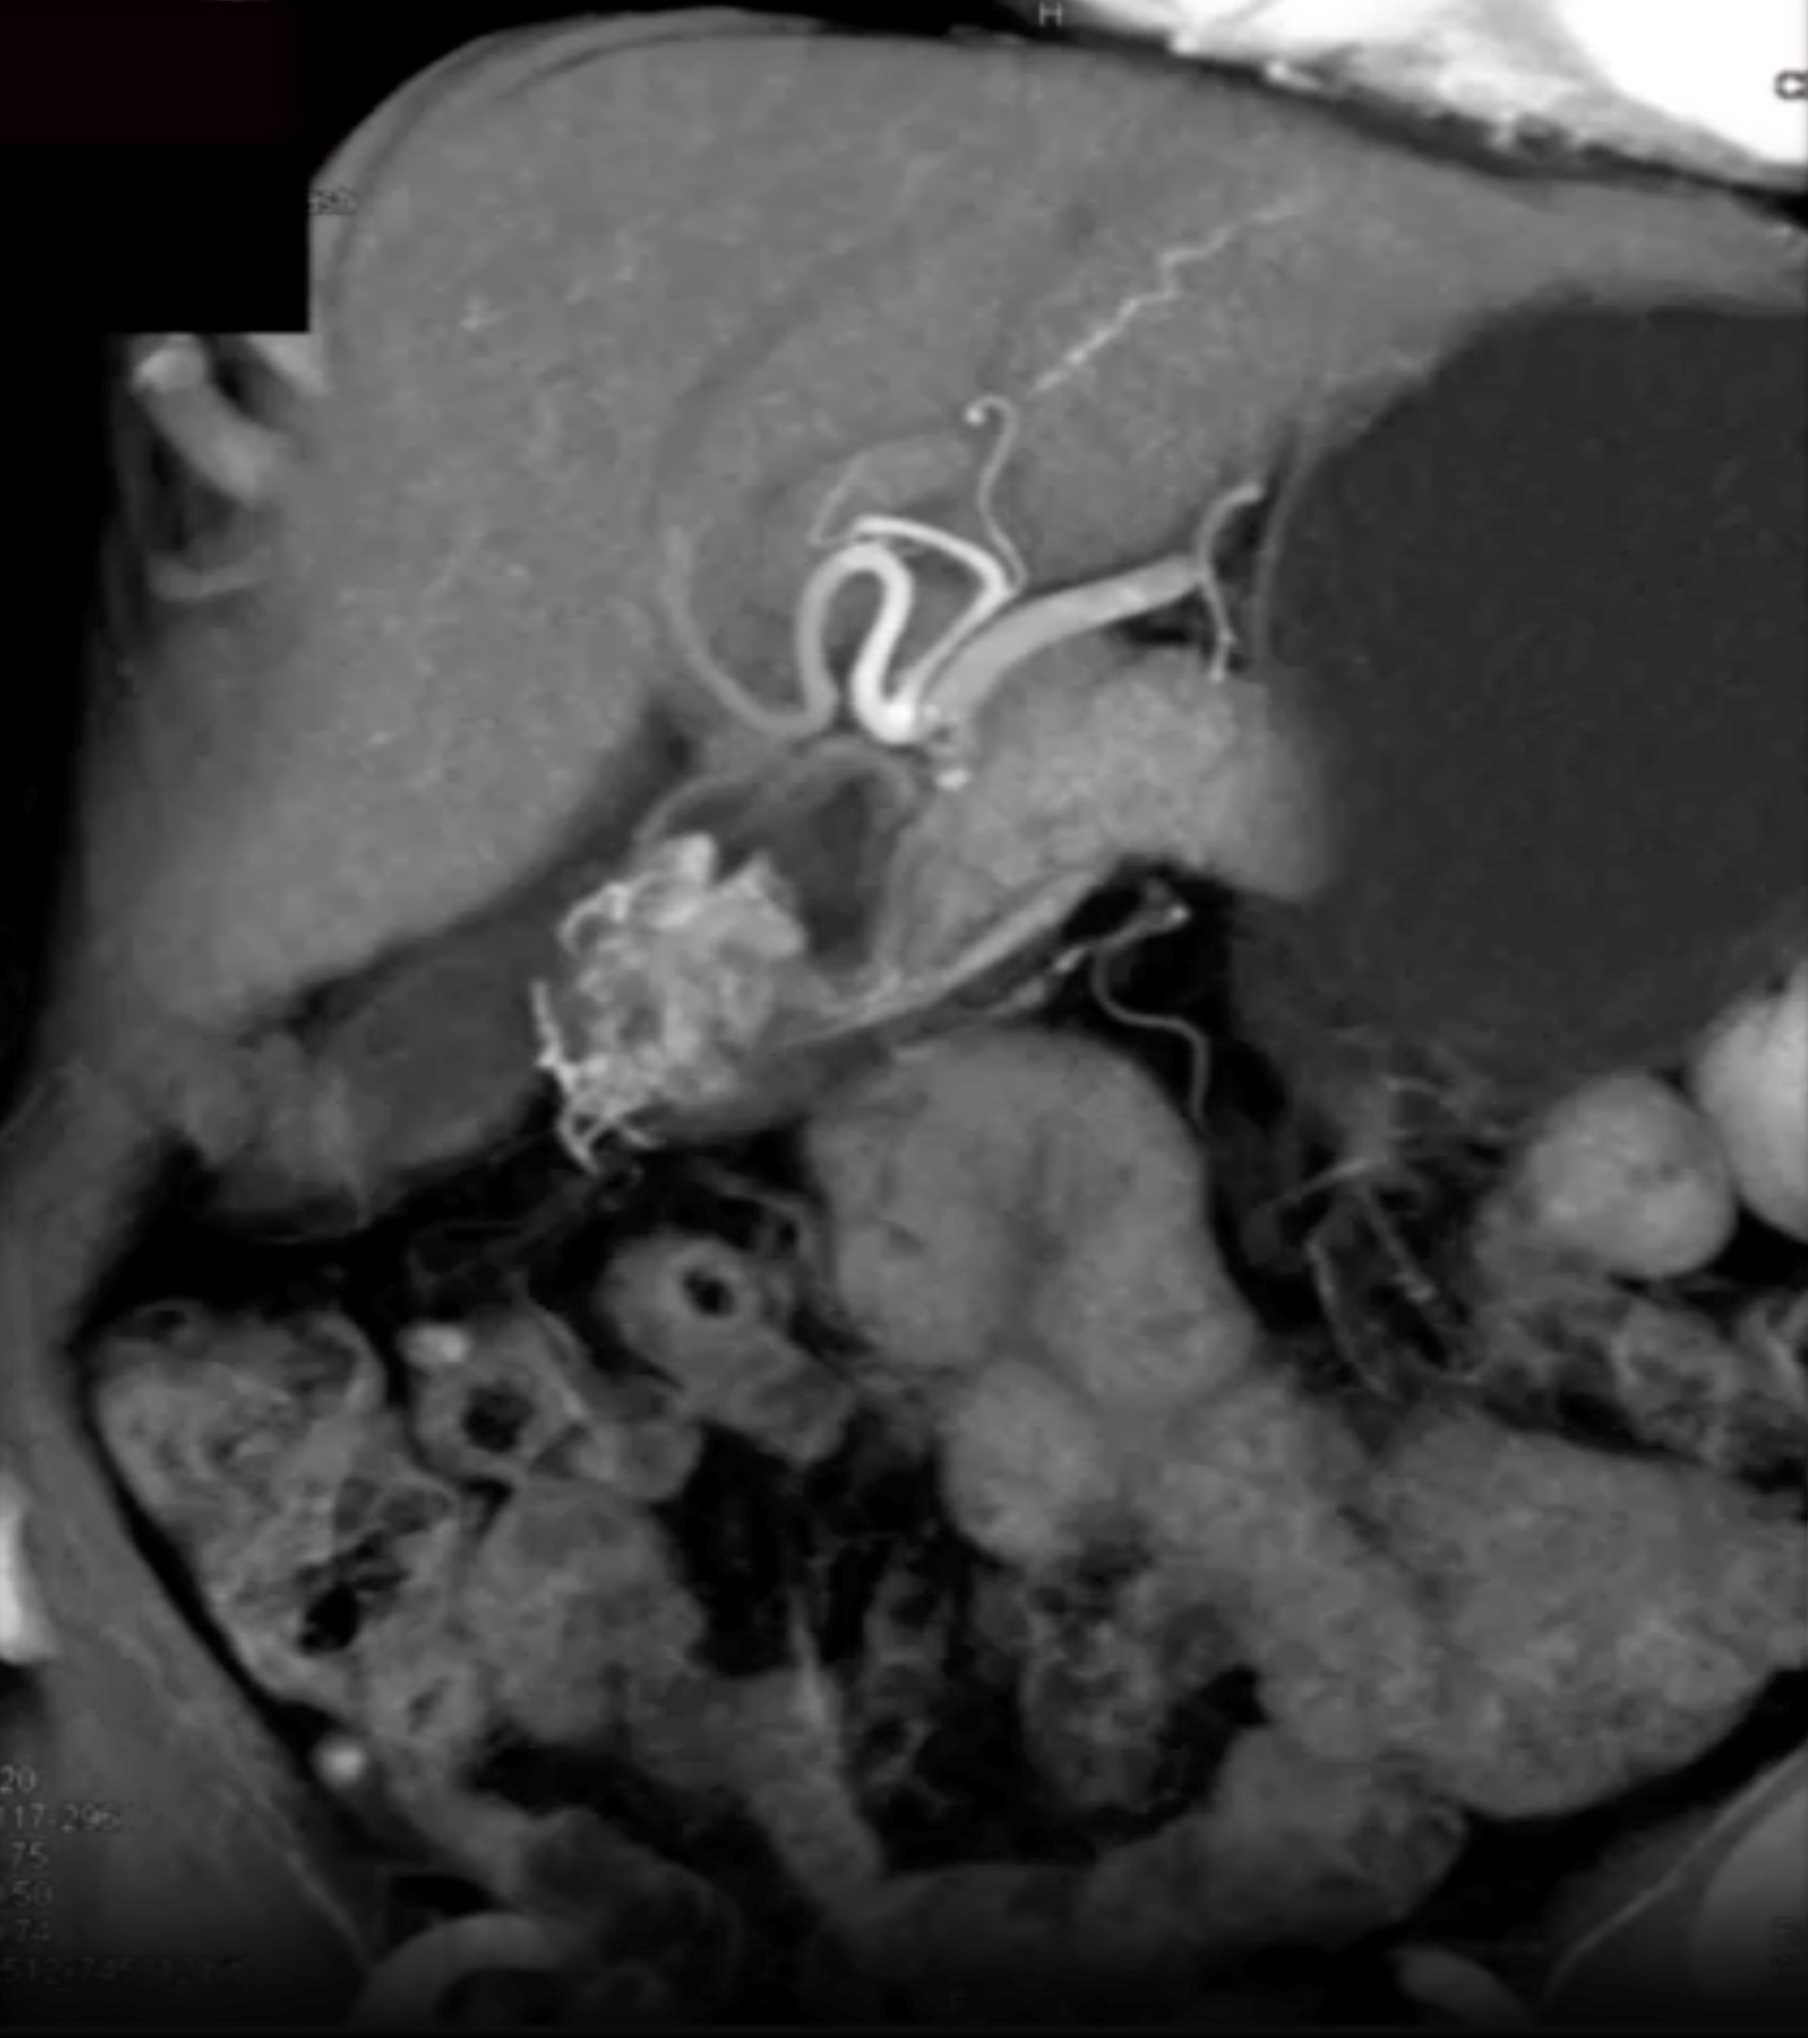

Watermelon Stomach (Gastric Antral Vascular Ectasis)